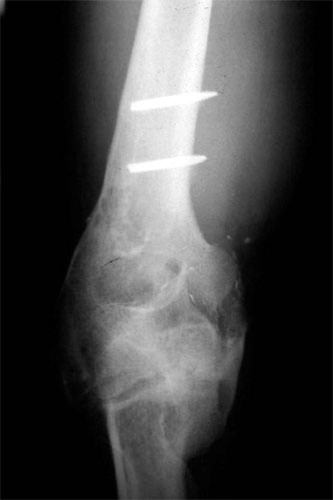

E.R. is a 26 year old male lifeguard who had a severe, unfortunate accident the first time he ever mounted a motorcycle. He was in a coma for many months with head trauma and had fractured his right elbow and forearm at the time of injury. He developed a condition called Heterotopic Ossification which meant that multiple joints «froze-up» due to deposits of calcium in the joint capsules. He was not able to walk until both hips were operated on by an internationally known hip surgeon who then referred him to Dr. Badia to address the stiff Right elbow and deformed forearm. In fact, at the initial visit, the patient stated that he had not moved the right elbow AT ALL for nearly 4 years and was unable to feed or groom himself with that hand. After a series of 3 operations to reconstruct both the elbow and forearm, this young man has gone back to swimming, work and a normal lifestyle.

The pictures depict the application of the dynamic external fixator, which stabilized and provided early motion to the rigid elbow after aggressive release of the capsule and bone excision.